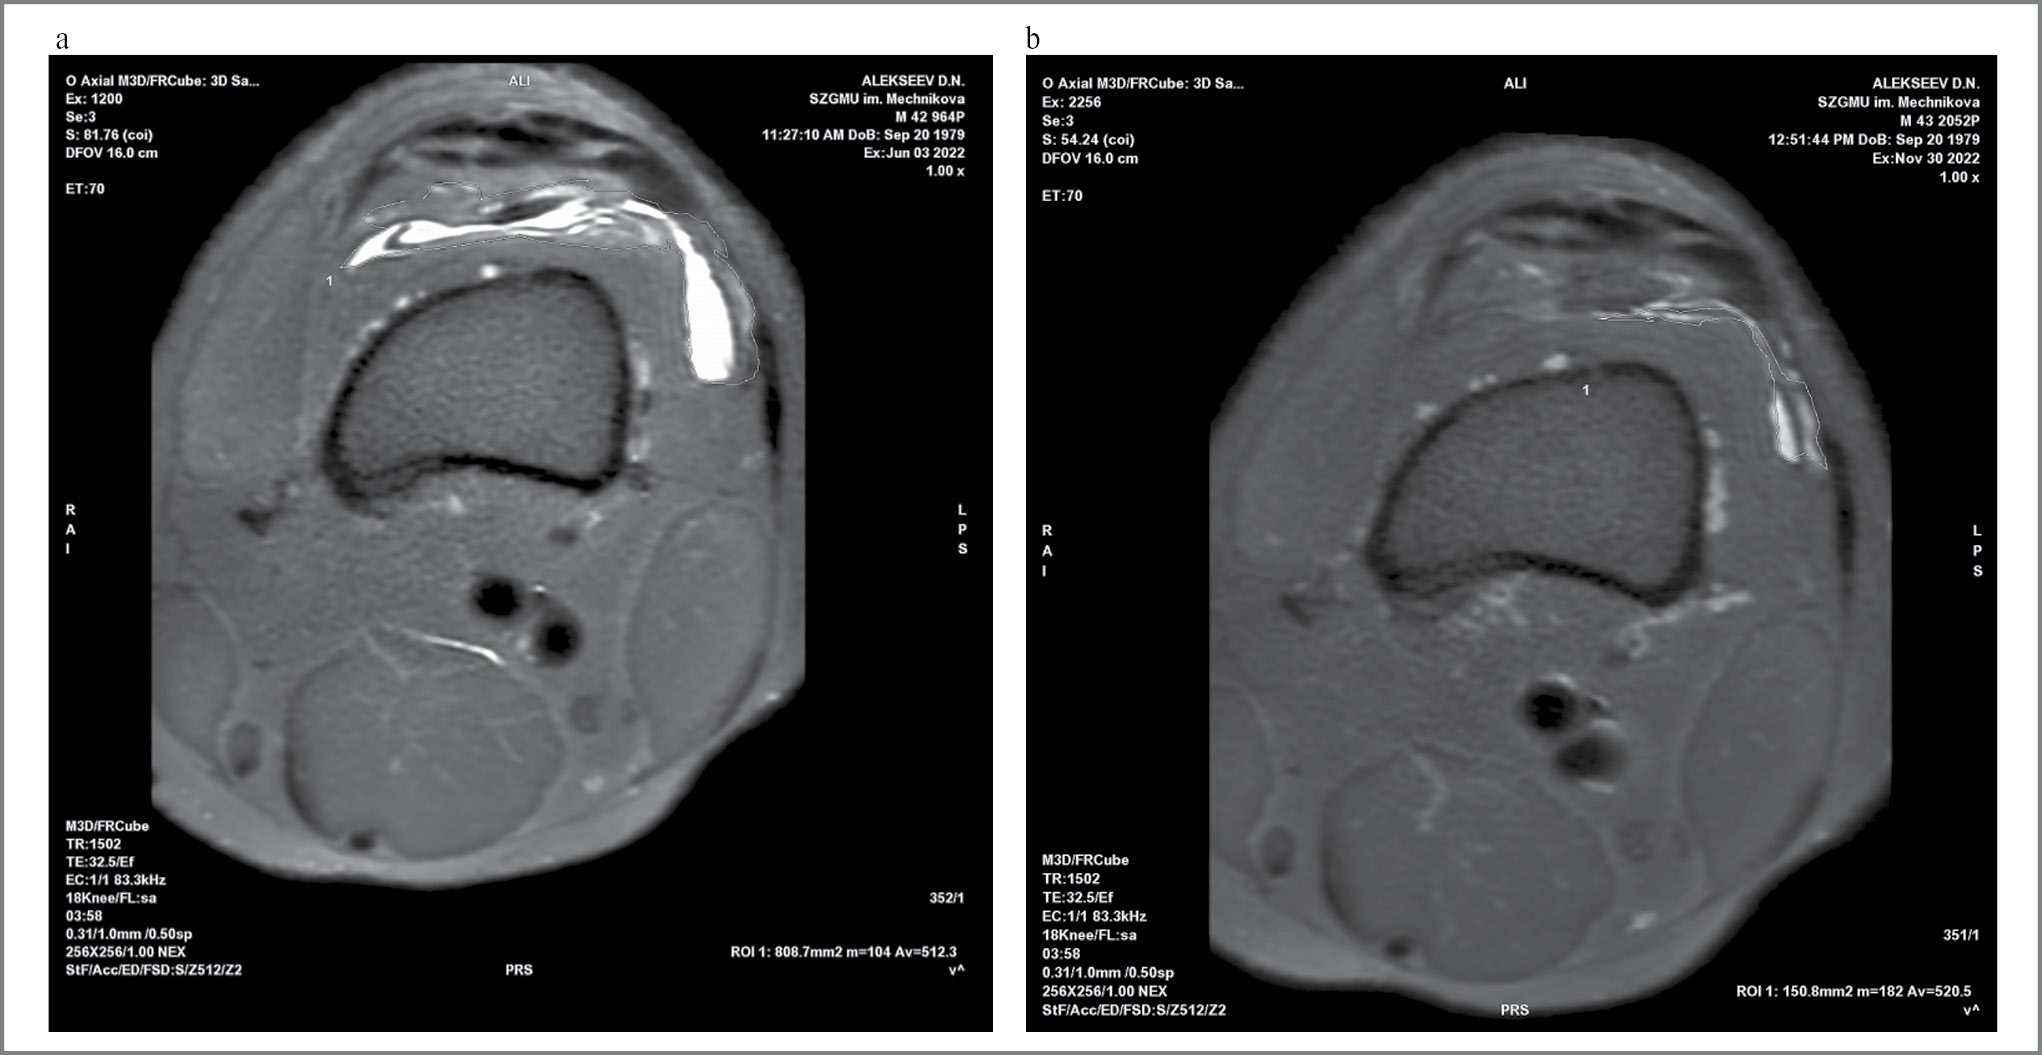

На рис. 8 представлен репрезентативный случай из исследования с уменьшением площади синовита на фоне терапии АН более чем в 5 раз.

Рис. 8. Площадь синовита у пациентки В. на фоне терапии АН через 6 мес: a – визит 2, площадь синовита – 8,1 см2; b – визит 9, площадь синовита – 1,5 см2.

Fig. 8. Area of synovitis in patient V. during Artneo therapy after 6 months: a – visit 2, area of synovitis 8.1 cm2; b – visit 9, area of synovitis 1.5 cm2.